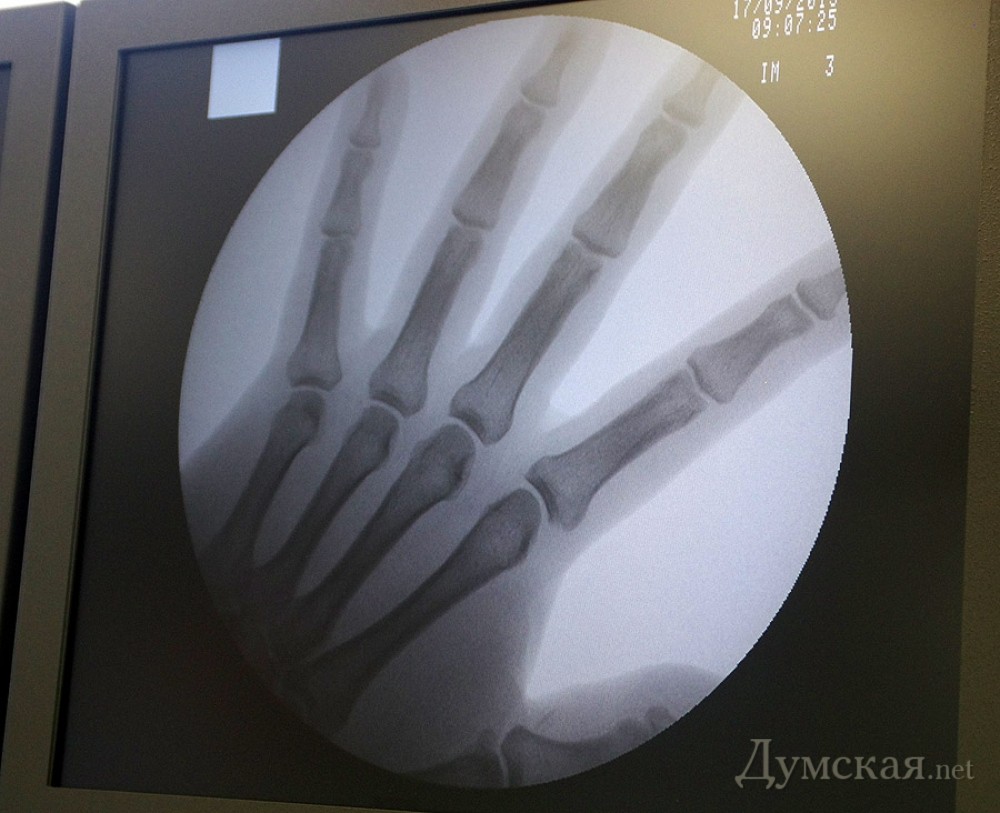

Медицинский хай-тек: в новомодной одесской клинике готовятся провести первую операциюТеперь в Одессе есть не только где с шиком умереть, но и шикарно подлечиться. И еще не факт, что второе будет дороже первого. В любом случае, сегодня в новой частной больнице, пафосно именуемой «Медицинский Дом «Одрекс», состоялась презентация возможностей нового стационарного отделения. Одновременно здесь могут проходить лечение до 30 человек: есть 20 стационарных коек, плюс 10 мест для интенсивной терапии. По новеньким коридорам толпу любопытных журналистов водил Сергей Калинчук, новый директор «Медицинского дома», экс-начальник горуправления здравоохранения, а еще ранее — главврач областной клинической больницы. С искрой в глазах и оживленно жестикулируя, он рассказывает о всевозможных направлениях работы нового отделения, а также о тактико-технических характеристиках того или иного аппарата. Что, как, в каком месте и с какой точностью может вас сшить, спаять, прочистить или отрезать что там у вас лишнее выросло… В общем, детали узнавать совсем не хотелось. Зато очень порадовало отношение специалиста к тому, как выглядит вверенное медицинское учреждение. Снаружи и в фойе оно больше похоже на какой-нибудь отельчик: симпатичные девочки на входе, диванчики, тарелка с яблоками Изнутри же – это футуристическая больничка из сериала о докторе Хаусе, собранная с фанатичной скрупулезностью по отношению к деталям. Зайти сюда можно только через специальные стерилизационные шлюзы. Стены и пол – из непонятного материала, напоминающего монолитный кусок гладкого пластика, на котором микроб явно не задержится. Градация помещений по уровню допуска, направление потоков пациентов, вентиляция воздуха на невообразимом для наших степей уровне – внутри не пахнет ничем, хотя ремонт только закончен. В общем, если медицинскую компоненту можно адекватно оценить, только будучи специалистом (или пациентом), то уровень менеджмента, понятный простому смертному, – впечатляет. Первую операцию в новом «Одрексе» проведут только в следующий понедельник. Ближайшую неделю помещения будут отмывать от следов пребывания журналистов, хотя персонал уже наготове. «Для меня это переход на новый уровень развития, — рассказывает заведующий стационарным отделением, сосудистый хирург Александр Смирнов. – Здесь открываются перспективы профессионального роста и появляется возможность более качественно оказывать помощь пациентам». СМЕРТЬ РОСІЙСЬКИМ ОКУПАНТАМ! ![]() Аппарат искусственной печени и почки. Работает в автономном режиме, не требуя, например, специально подготовленной воды ![]() Разноцветный свет - не для празднования Нового года, а для того, чтобы светить светом разной температуры. Это обеспечивает хорошую видимость в полости операционной раны ![]() Заведующий стационарным отделением, сосудистый хирург Александр Смирнов показывает единственный в Украине аппарат, который позволяет спаивать нервные окончания ![]() Красная линия здесь неспроста: отделение поделено на несколько зон доступа. В каждой - разные стандарты по санитарной обработке ![]() Александр Борисович - главный человек в новом отделении. И интерна жизни научит, и то, что оторвалось, куда надо пришьет Помітили помилку? Виділяйте слова з помилкою та натискайте control-enter |